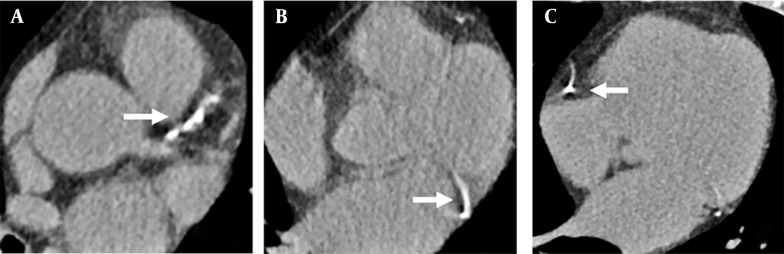

Abstract Image